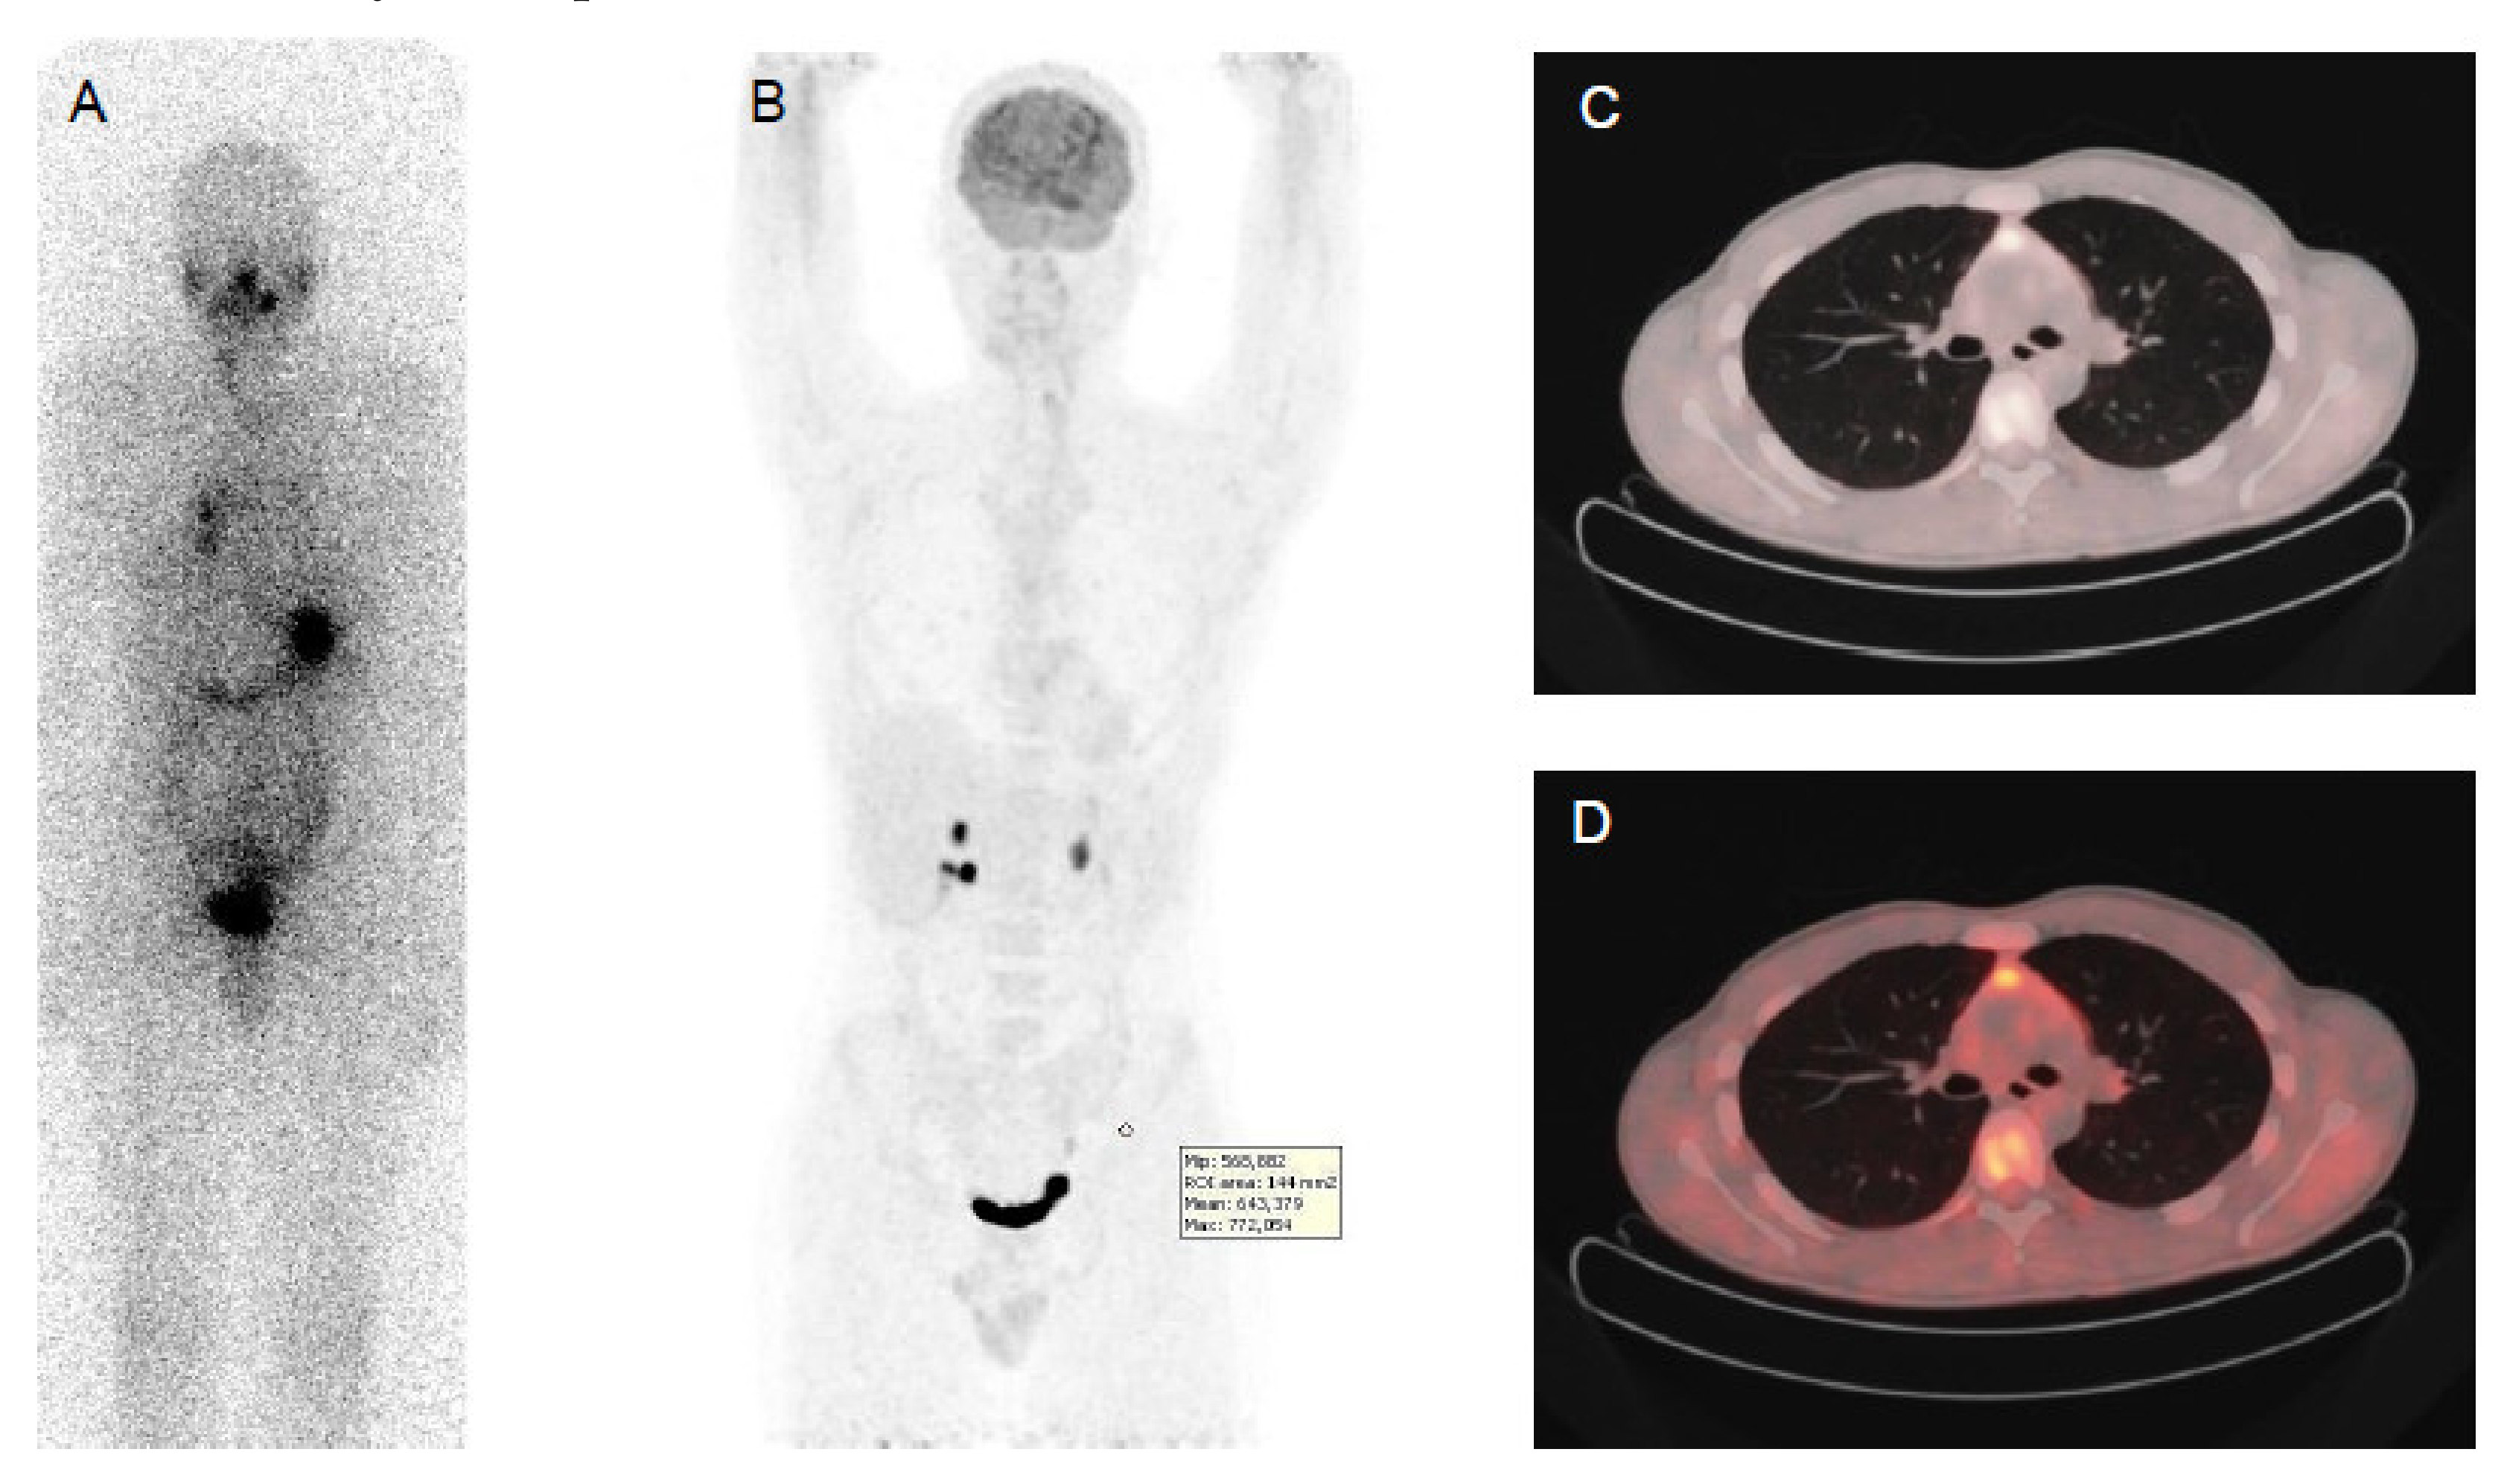

Figure 1.

Papillary thyroid cancer in a 41-year-old man with a high thyroid stimulating hormone stimulated serum thyroglobulin level (475 ng/mL). Post-therapy (A) 131I whole-body scan showed pulmonary uptake and uptake and in neck lymph nodes. 18F-FDG PET-CT (B,C,D): CT images evidenced multiple small millimetric lung metastases (B,C,D), without significant 18F-FDG uptake.

The sensitivity of 18F-FDG PET/CT increases with higher serum Tg levels and with larger size of the tumor foci. Nevertheless, in case of highly proliferating disease and in those with a short Tg doubling time, the sensitivity can be very high, even in the presence of low Tg levels [71]. 18F-FDG uptake can be detected in neck lymph nodes, even in nodes of less than 1 cm in diameter, in lung and in bone metastases. However, PET scan failed to detect abnormal 18F-FDG uptake in small miliary lung metastases detected by CT scan, due to an absence of 18F-FDG uptake in these well differentiated and slow growing neoplastic cells, and partial volume effect, consisting of the combined effect of poor spatial resolution and the contamination of activity from neighboring tissues or spillover effect (Figure 1) [72,73].